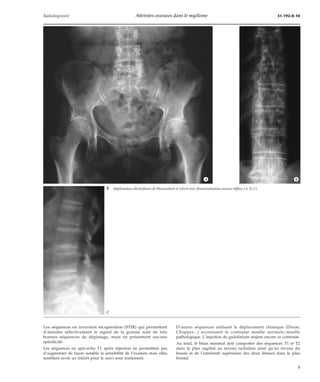

D’autres séquences utilisant le déplacement chimique (Dixon,

Chopper...) accentuent le contraste moelle normale/moelle

pathologique. L’injection de gadolinium majore encore ce contraste.

Au total, le bilan minimal doit comporter des séquences T1 et T2

dans le plan sagittal au niveau rachidien ainsi qu’au niveau du

bassin et de l’extrémité supérieure des deux fémurs dans le plan

frontal.